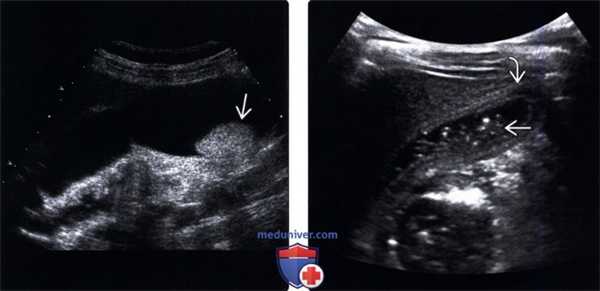

(Левый) На продольном УЗ срезе визуализируется желчный пузырь, содержащий не отбрасывающий тени опухолевидный сладж.

(Правый) Положение пациента на боку. На продольном срезе в просвете желчного пузыря определяются подвижные множественные флотирующие эхо-сигналы. Обратите внимание на почти спавшийся желчный пузырь и выраженное утолщение его стенки.